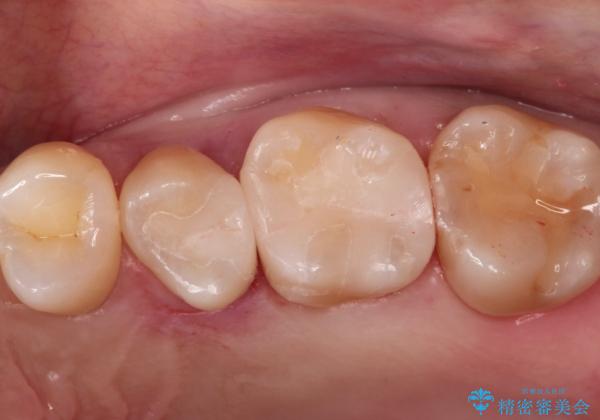

【セラミックインレー】定期検診で見つかった虫歯。

- 歯と歯の間で見つかりづらい虫歯でしたが、顕微鏡で確認し患者様に説明することで理解していただき、セラミックインレーにて修復治療を行いました。

劣化の少ないセラミックインレーを選んでいただき、色調にも満足していただきました。